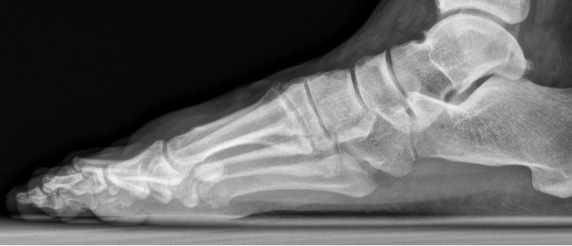

Ein Röntgenbild kann die Diagnose schliesslich sichern. Darauf ist sichtbar, dass der Gelenkspalt verschmälert ist, da sich der Knorpel abgenutzt hat. Zudem lassen sich die typischen Osteophyten und Überlastungen am gelenkangrenzenden Knochen in Form von Skleroselinien (Knochenverhärtung) und Zysten identifizieren.